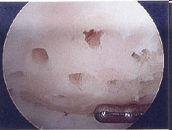

C. Les microfractures pour réparer le cartilage

Définition: réparation d’une lésion cartilagineuse par la réalisation d’orifices favorisant la formation d’un tissu fibrocartilagineux, une sorte de patch.

Suites opératoires : la revalidation nécessite une absence d’appui pendant 6 semaines puis le port d’une attelle de décharge pendant 6 semaines